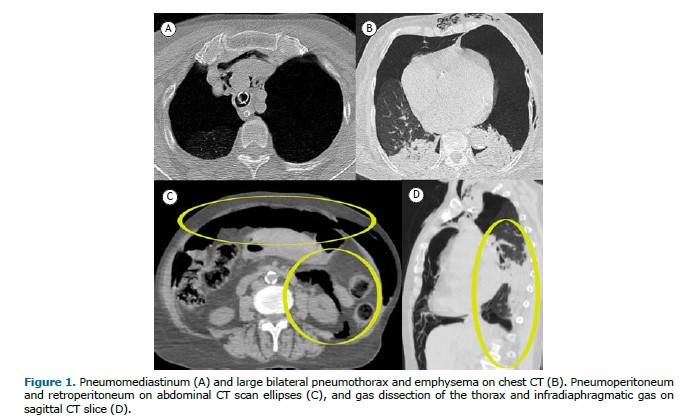

An 80-year-old woman with systemic arterial hypertension was admitted to the emergency department after a transient loss of consciousness. On arrival, she presented with hypoxemia and decreased sensorium, requiring orotracheal intubation. Chest computed tomography (CT) revealed a large bilateral pneumothorax, pneumoperitoneum, and retroperitoneal air (Figure 1). A chest tube was placed. An initial suspicion of hollow viscus perforation was ruled out after exploratory laparotomy showed no visceral injury. The combination of imaging findings and clinical context strongly suggested barotrauma secondary to excessive positive-pressure ventilation. This likely resulted in alveolar rupture due to elevated intrathoracic pressure, with air dissecting along bronchovascular sheaths—a phenomenon known as the Macklin effect. From the lungs, air extended into the mediastinum and, in rare cases, progressed as gas dissection through mediastinal vessels into the retroperitoneal space and peritoneal cavity, leading to pneumoperitoneum without visceral perforation. The patient subsequently developed an ischemic stroke and died following clinical deterioration.

Pulmonary barotrauma is uncommon but potentially life-threatening, resulting from sudden increases in intrathoracic pressure. Common complications, such as hypoxemia and subcutaneous emphysema, are typically managed conservatively. However, gas dissection into the retroperitoneum and peritoneum, though rare, represents a serious and diagnostically challenging condition. Early recognition through CT is essential for timely and appropriate management.(1–2)